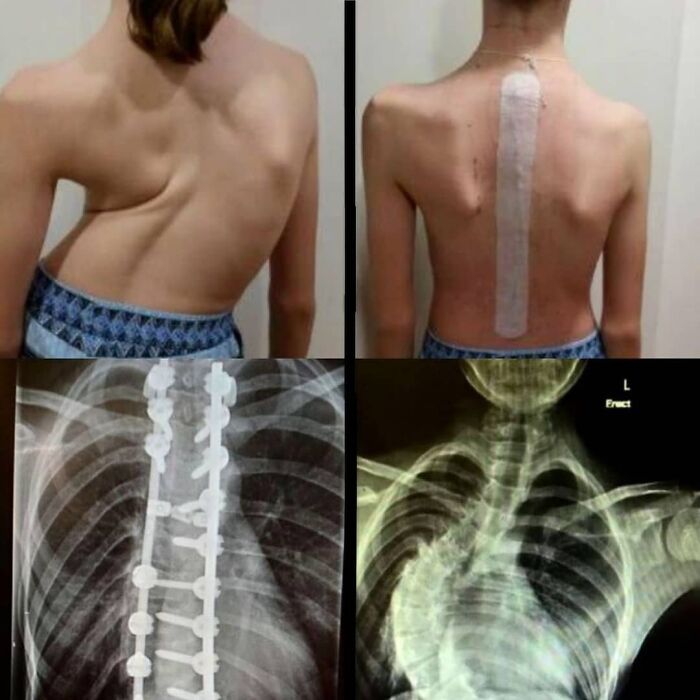

#23 Case Of A 13-Year Old Girl With Severe Scoliosis

This 13-year-old’s scoliosis was progressing so rapidly that major spinal surgery was her only treatment option. In just over six months, her curve progressed from what was initially 49-degree to a 99-degree curve. The girl now has a combination of titanium rods and screws around her spine. Luckily she fully recovered and got back to her normal activities. Scoliosis is a sideways curvature of the spine that occurs most often during the growth spurt just before puberty. While scoliosis can be caused by conditions such as cerebral palsy and muscular dystrophy, the cause of most scoliosis is unknown. About 3% of adolescents have scoliosis. Treatment depends on the degree of curve, location, and cause. Minor curves may simply be watched periodically.Treatments may include bracing, specific exercises, and surgery. The brace must be fitted to the person and used daily until growing stops. Specific exercises may be used to try to decrease the risk of worsening. They may be done alone or along with other treatments such as bracing. Evidence that chiropractic manipulation, dietary supplements, or exercises can prevent the condition from worsening is weak. However, exercise is still recommended due to its other health benefits. Surgery is usually recommended by orthopedists for curves with a high likelihood of progression (i.e., greater than 45 to 50° of magnitude), curves that would be cosmetically unacceptable as an adult, curves in people with spina bifida and cerebral palsy that interfere with sitting and care, and curves that affect physiological functions such as breathing. To completely straighten a scoliotic spine is usually impossible, but for the most part, significant corrections are achieved.

Image credits: medicalpedia